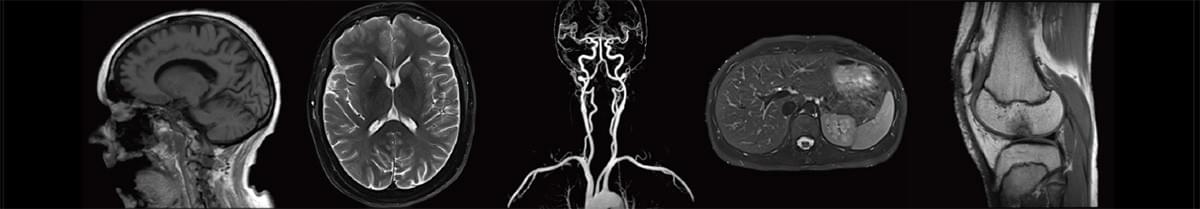

MRI 磁共振是一种利用磁场将体内的情况画像化的检查,对病变部位及病变性质诊断十分有效。兵库医科大学梅田健康医学中心率先引进目前业界最先进的德国西门子 Siemens Healthineers 3.0T MRI设备,相比较于一般广泛使用的机种(1.5T),MRI3.0T仪器可以拍摄出更详细鲜明的影像。由于在高层建筑中放置大型仪器难度很高,兵库医科大学梅田健康医学中心是日本首家在高层建筑中放置此仪器的体检中心。

3.0T磁共振扫描仪是世界先进的临床科研型磁共振之一,采用人工智能的生物感知激发技术,是应用于全身扫描的超高场磁共振成像仪,开创了全身系统性疾病诊断的临床应用新领域。具有扫描速度快、检查时间短、图像质量好、诊断精准度高的优势,配备的超大魔毯线圈还可以根据受检者具体情况选择合适的扫描体位,提升舒适度。与普通核磁共振相比,具备更快速、高清的成像系统,对组织的形态及病理改变具有高敏感性,利于捕捉到微小的病变结构,能够方便、快捷、准确发现早期病灶,提高病灶检出率,为实现疾病的早发现、早诊断、早治疗和实现临床、科研和教学新突破提供有力保障。同时,可大大缩短检查时间,减少误差和伪影,使检查更加方便快捷。

3.0T磁共振扫描仪广泛运用于神经系统、胸部、腹部、盆腔、心血管、骨骼关节、软组织、乳腺等全身各部位磁共振检查。 该设备的不同序列能够对组织结构和病灶进行多角度、多方位观察,利于病灶定性分析;高清血管重建可更好地判断肿瘤血供,规划手术路径;对全身各部位动静脉进行成像,对各种原因导致的血管狭窄、动脉瘤、动脉夹层等血管性疾病有良好的检查效果,与其他磁共振相比,高清的血管壁成像能够清晰地显示动脉硬化斑块,有助于预防血管栓塞的发生和及时治疗;进行心脏的形态学检查,对心脏的运动和血液供应情况进行观察,对先心病、冠心病等各种心脏疾病有很好的检查效果;全身DWI成像及融合后处理技术,模拟全身PET- MRI检查,可用于全身体检及发现肿瘤原发灶、转移灶。